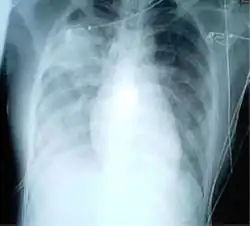

For a case to be considered probable, a chest X-ray must be indicative for atypical pneumonia or acute respiratory distress syndrome.

The WHO has added the category of "laboratory confirmed SARS" which means patients who would otherwise be considered "probable" and have tested positive for SARS based on one of the approved tests (ELISA, immunofluorescence or PCR) but whose chest X-ray findings do not show SARS-CoV infection (e.g. ground glass opacities, patchy consolidations unilateral).[12][13]

The appearance of SARS-CoV in chest X-rays is not always uniform but generally appears as an abnormality with patchy infiltrates.[14]